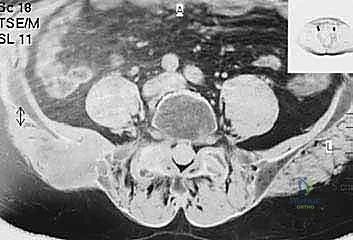

- التصوير بالرنين المغناطيسي (MRI): الفحص الأفضل لتقييم امتداد الورم خارج العظم إلى الأنسجة الرخوة (العضلات، الأوعية الدموية، الأعصاب) وتقييم مدى إصابة نخاع العظم.